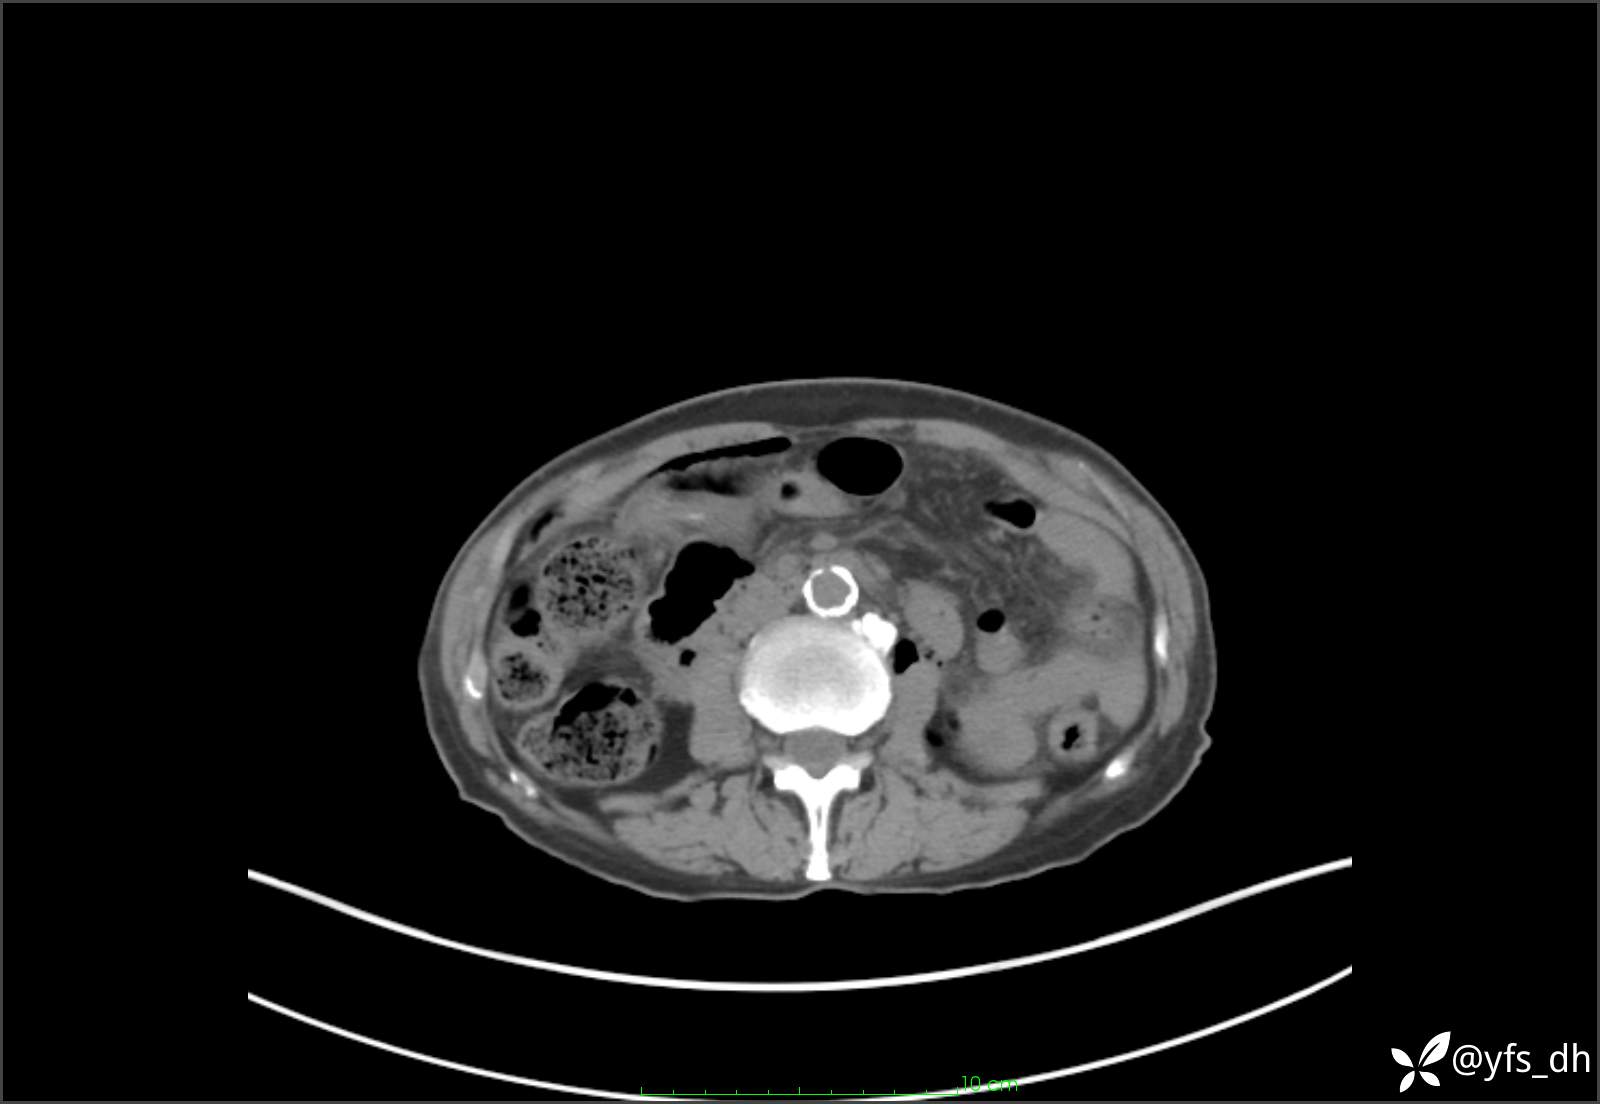

1.简要病史:患者4天前突发上腹部疼痛不适,但可以忍受。3小时前饭后突然加重,不能忍受后就诊。

2.简要手术记录:术中见腹盆腔大量肠液及粪便,乙状结肠中下段见一约3cm的破口。